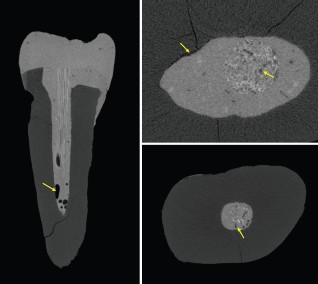

The X4 POSEIDON modular micro-CT system is equipped with a high resolution sCMOS detector that is ideal for examination of the microstructural integrity of teeth and dental restorations (Figures 2, 3 and 4). The X4 produces high-quality images from the outer to innermost structure of the tooth. In restorative dentistry, a key application is the study of the marginal and internal fit of filling materials, where research shows that the material type significantly influences the adaptability of the restoration, with some materials achieving lower marginal and internal gap values.

Voids, gaps, and bubbles can reduce the mechanical properties of resin-based materials. The original structure of the restorative material may have appropriate mechanical properties, but defects can reduce the performance of the restorations and decrease the durability of the restorative material.